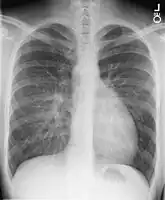

Chest X-ray: On chest X-ray (CXR), transposition of the great vessels typically shows a cardio-mediastinal silhouette appearing as an "egg on a string ", in which the enlarged heart represents an egg on its side and the narrowed, atrophic thymus of the superior mediastinum represents the string.[9]

- X-ray showing characteristic finding in case of transposition of the great vessels which is called egg on side sign